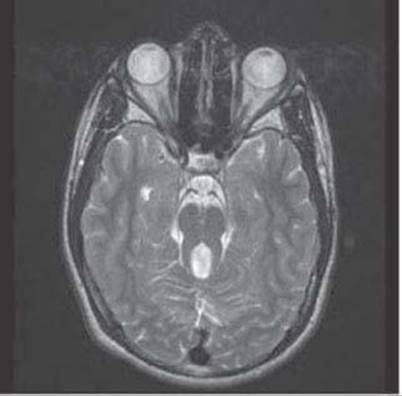

23. A 2-year-old boy with developmental delay and ataxia presents for evaluation. He has extraocular muscle abnormalities, but visual acuity is unaffected and his irises appear normal. MRI of the brain is done, and an image is shown in Figure 14.2. What is the most likely diagnosis in this patient?

FIGURE 14.2 Axial T2-weighted MRI. Courtesy of Dr. Manikum Moodley and Dr. Gary Hsich

c. Joubert syndrome